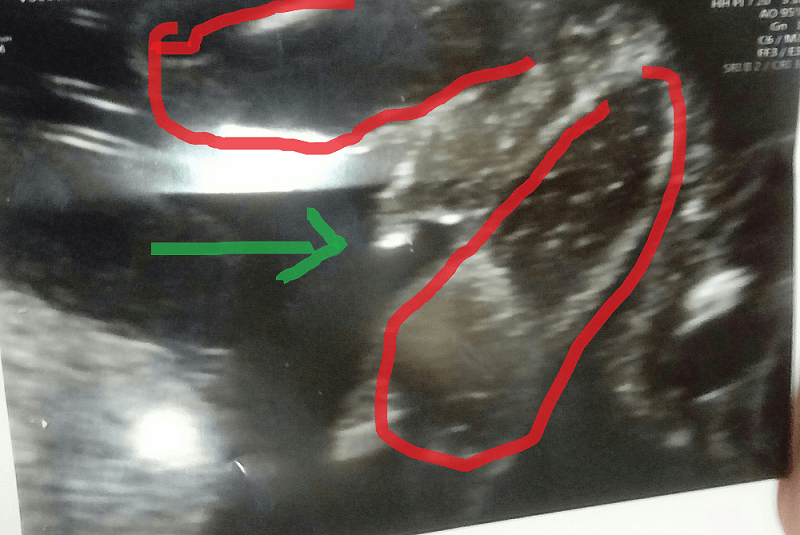

Przypomina wam to siusiaka? Przyszłe mamusie chłopców też u was to tak wyglądało?